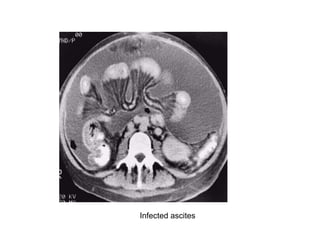

Infected ascites

Ascites, secondary to cirrhosis of the liver, may become

infected spontaneously.